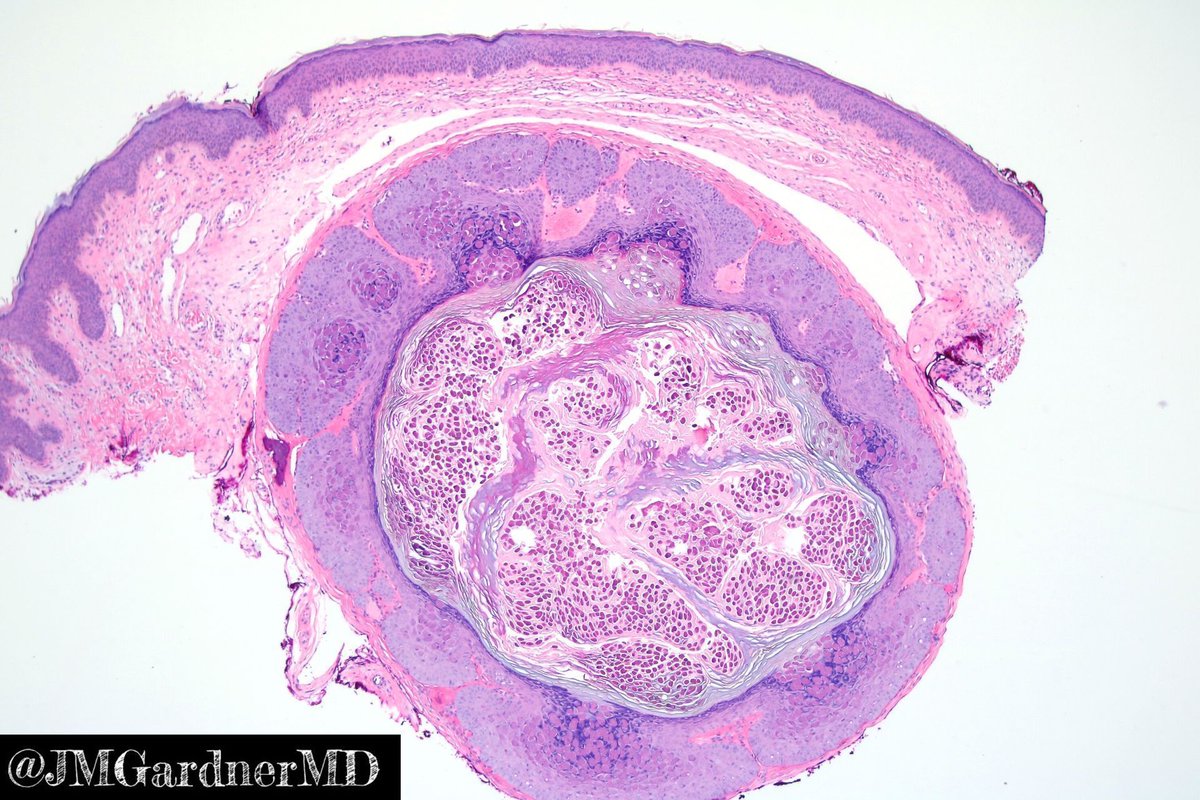

Jerad Gardner, MD (@jmgardnermd) 's Twitter Profile Photo

Cyst from the thigh of a child. Your diagnosis? Answer here: youtu.be/APVCziUvL2g?si…. #pathology #pathologists #pathTwitter #dermpath #dermatology #dermatologia #dermtwitter